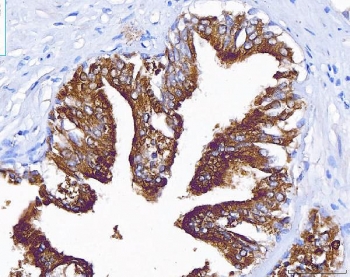

IHC staining of FFPE human prostate cancer tissue with ACP3 antibody. HIER: boil tissue sections in pH8 EDTA for 20 min and allow to cool before testing.